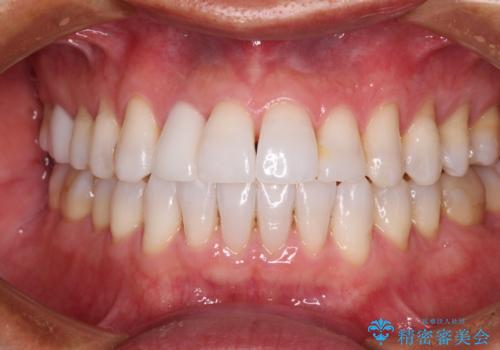

- 前歯の矮小歯と捻れや変色を気にして来院された患者様です。

結婚式が近いということもあり、前歯4本をオールセラミッククラウンにて補綴治療することとしました。

前歯の捻れは、オールセラミッククラウンよりも矯正治療による改善の方が、歯を削らなくて済むためお勧めとなります。

しかし、矮小歯の改善はオールセラミッククラウンでの補綴治療が必要であり、幅径のバランスを取る必要があるため、4前歯の補綴治療を選択しました。